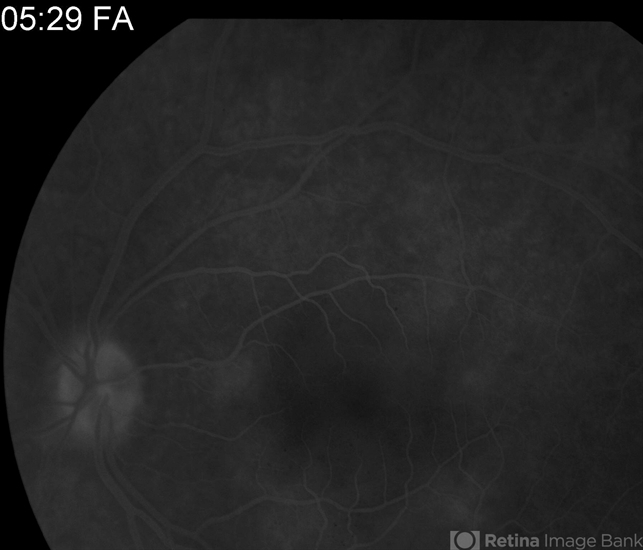

- acute multifocal placoid pigment epitheliopathy (AMPPE)

- 24-year-old female presented with central blurry vision for 3-5 days. Vision : OD 20/20, OS 20/100